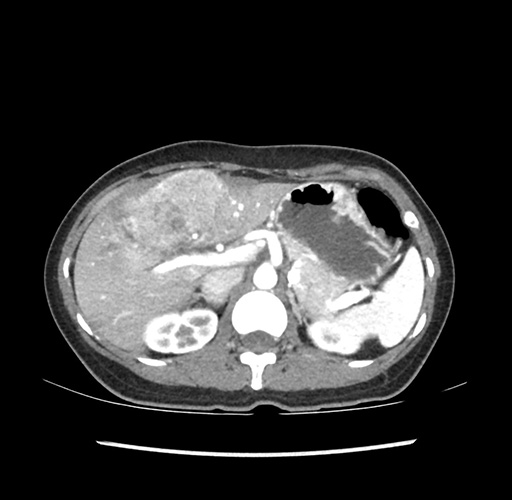

Imaging Analysis

Look through the patient's CT scan to identify any areas of concern for the necessary procedure.

Based on your CT findings, which issue(s) would give reason for "planned slowing down moment(s)" in this case?

Considering a standard left lateral sectionectomy procedure, what step(s) of the operation would you do differently in this case ?